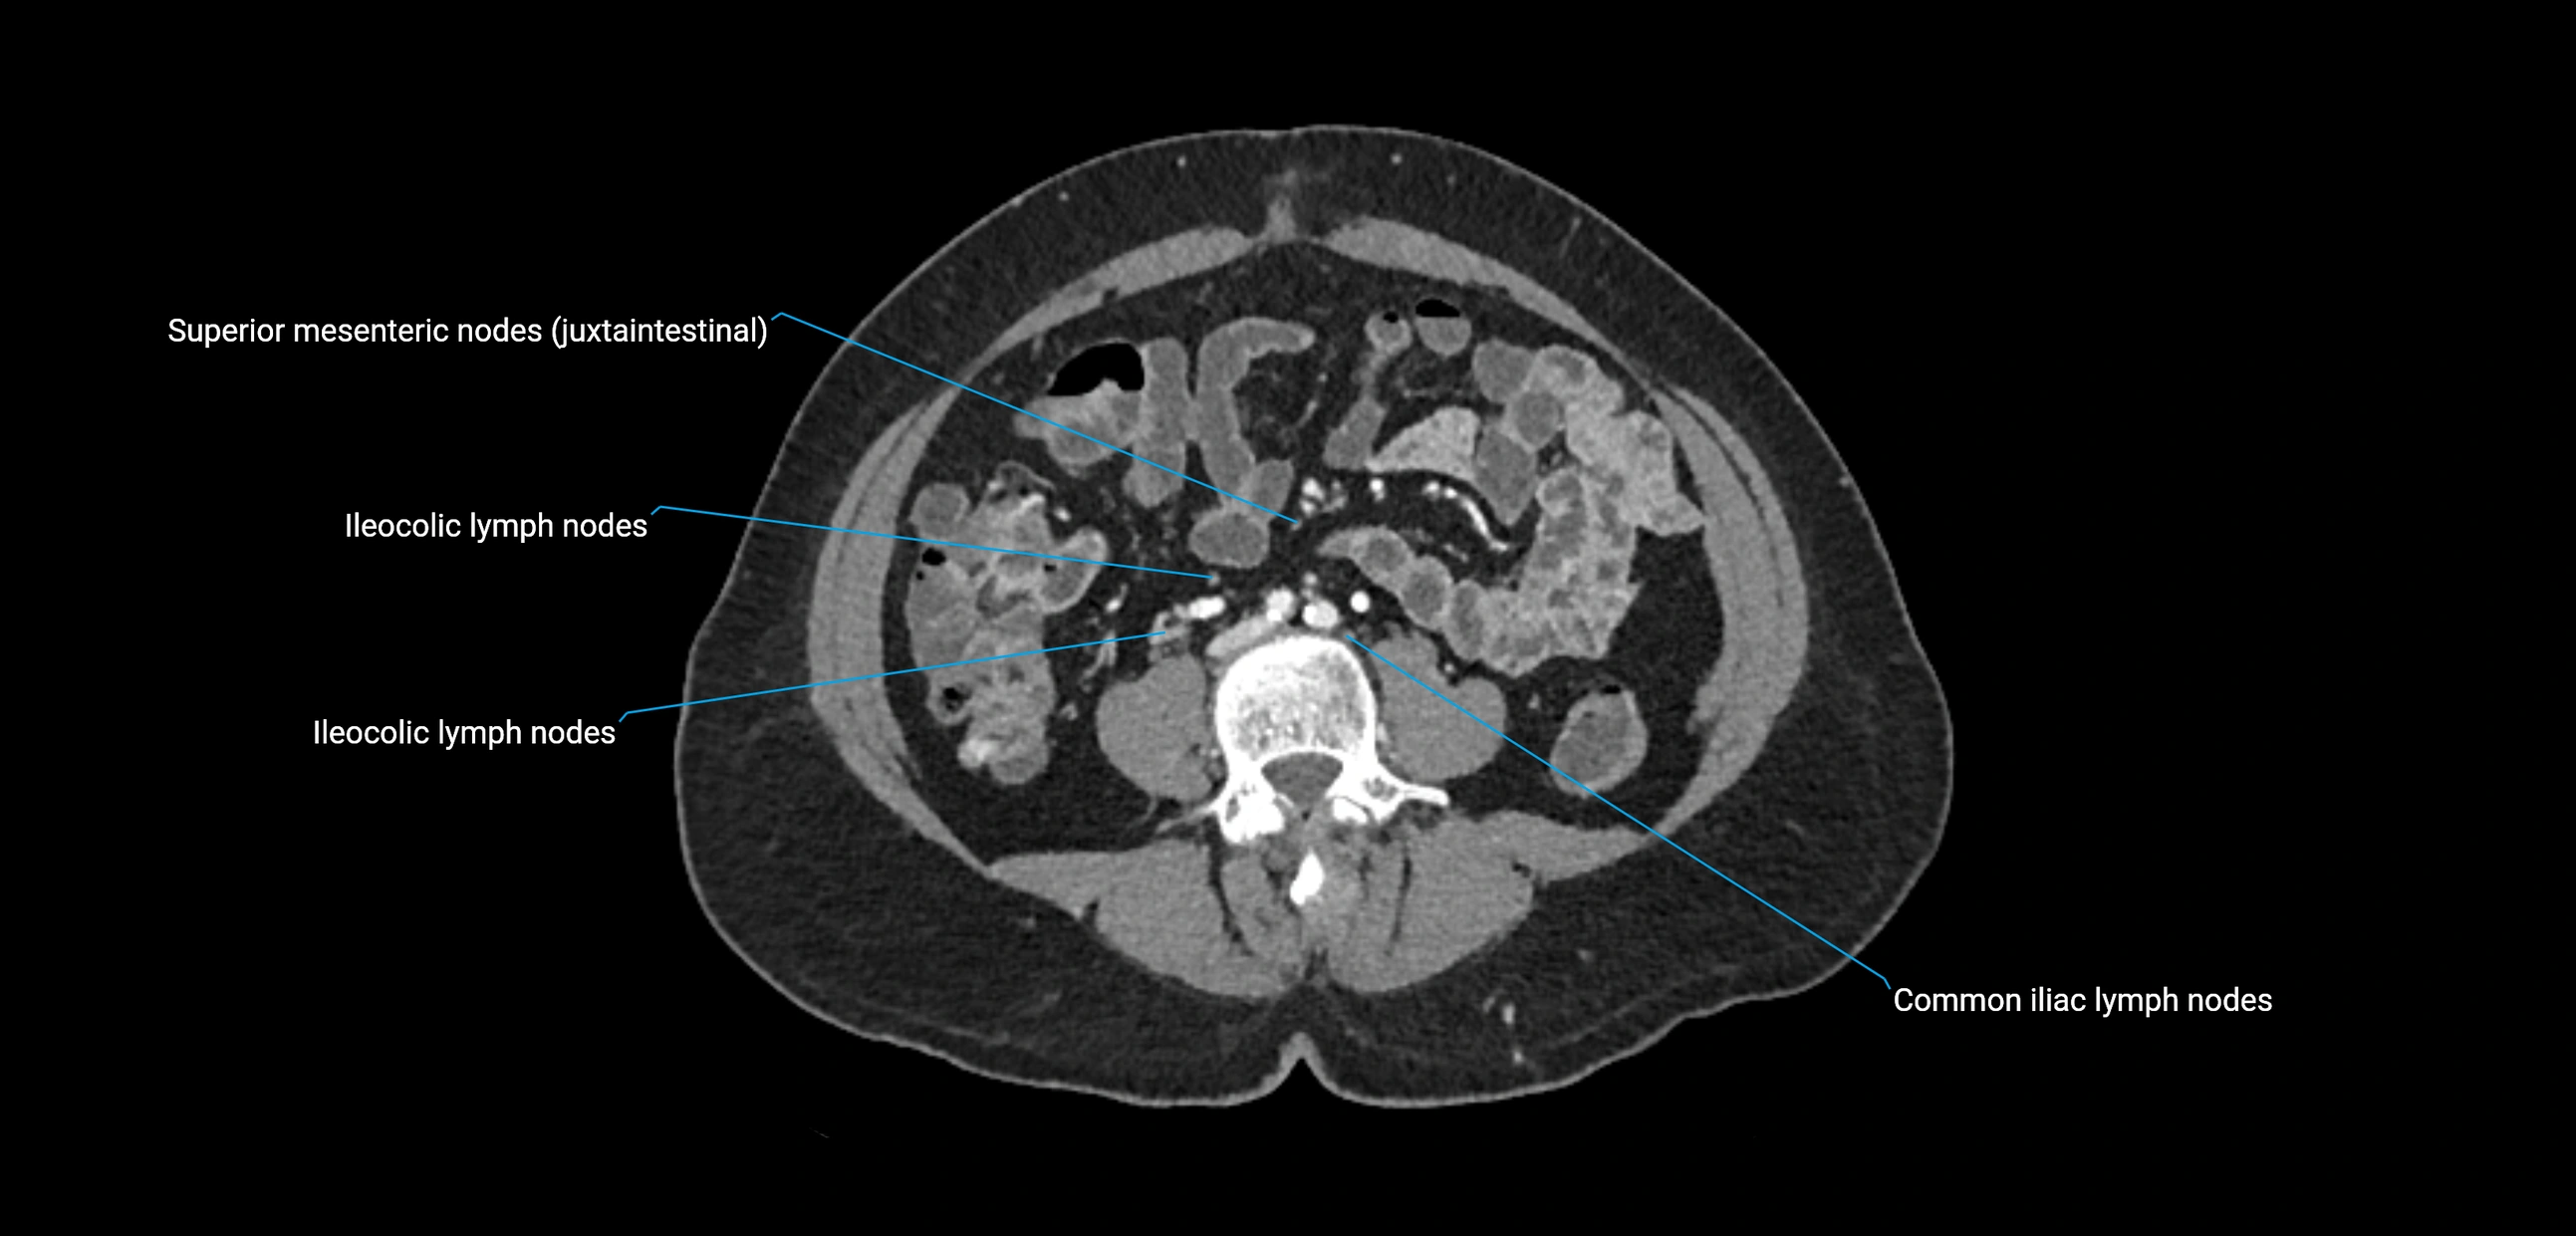

CT Appearance

CT Pre-Contrast:

• Nodes appear as soft-tissue density nodules adjacent to the aorta and IVC

• Calcification may be seen in chronic infections (e.g., tuberculosis)

CT Post-Contrast:

• Normal nodes enhance homogeneously

• Malignant nodes may show heterogeneous enhancement, central necrosis, or conglomerate formation

• Size >1 cm short axis is suspicious, though morphology and distribution are equally important